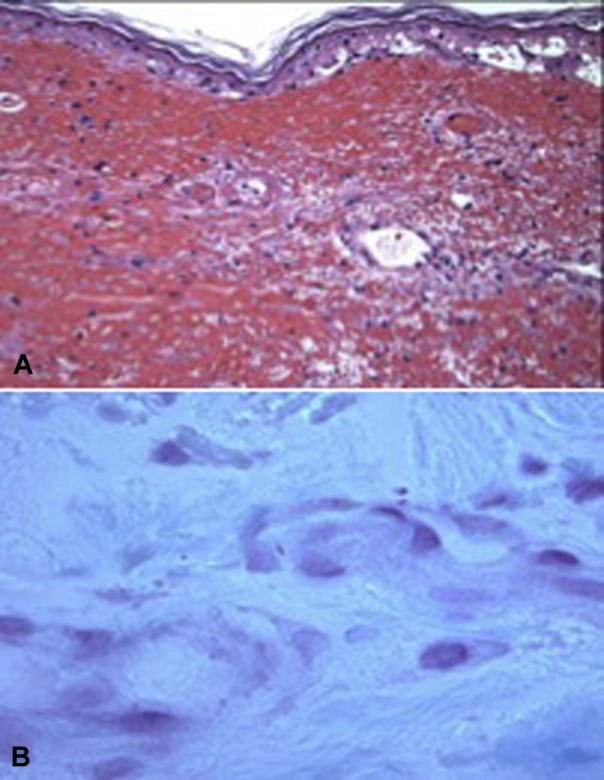

Fig 2.

A, Ischemic epidermal necrosis and fibrin thrombi occluding capillaries in the superficial dermis and focal perivascular fibrin deposition with scant neutrophils, pericytoplastic debris, and dermal hemorrhage. B, Extravascular gram-negative rods. (A, Hematoxylin-eosin stain, B, Gram stain; original magnifications: A, ×100; B, ×1000.)